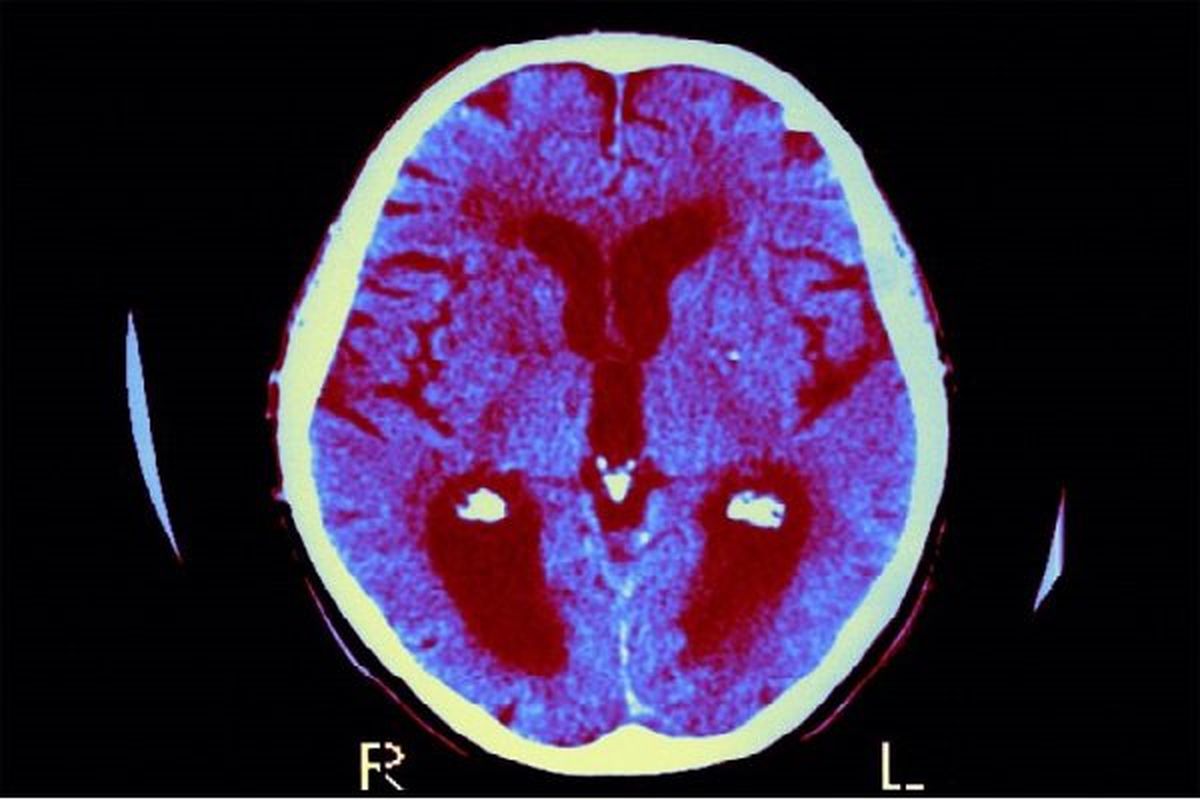

تیر ۳۰, ۱۴۰۴تیر ۲۹, ۱۴۰۴ - تکنولوژیفراموشی زودهنگام در کودکان؛ یک علت خطرناک_دانش دوست [ad_1] به گزارش دانش دوست ۲۸ تیر ۱۴۰۴ ۱۱:۴۴ بر پایه یک مطالعه تازه، قرار گرفتن در معرض سرب در دوران بارداری و اغاز کودکی امکان پذیر شدت فراموشی اطلاعات در کودکان را افزایش دهد و به طور بالقوه یادگیری و رشد شناختی را مختل کند. دسته بندی مطالب کسب وکار اخبار ورزشی اخبار اقتصادی فرهنگ وهنر سلامتی اخبار تکنولوژی [ad_2]